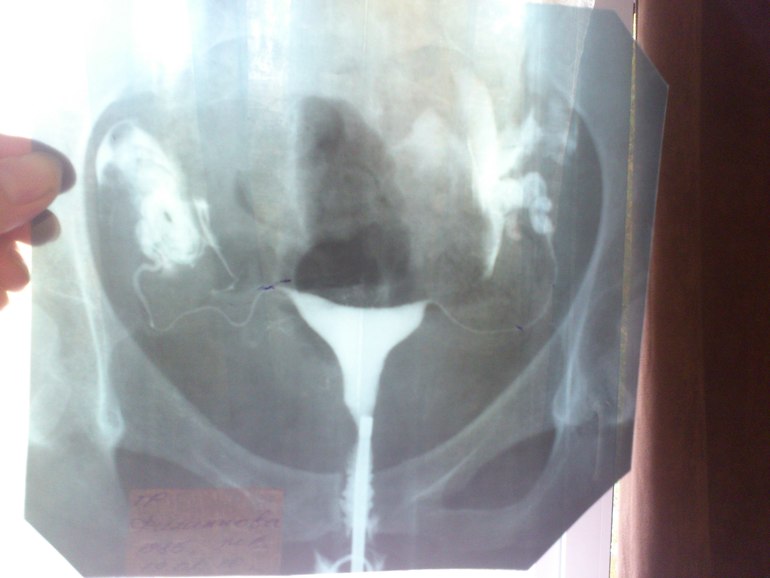

Девочки, скажите это нормально если по снимкам ГСГ трубы идут вверх, а не вниз????? Переживаю если мои яичники где-нибудь внизу, то яйцеклетка до них не доберется просто: ((

Мирис! У меня такая же проблема была и от этого мы не могли заБ! вот снимок

Это однозначно надо делать лапару! У меня после двухстороннего аднексита образовались спайки которые задрали вверх трубы! На операции все спайки рассекли и востановили все по местам и через 9 месяцев мы заБ!

если смотреть строение женских репродуктивных органов, то врят ли яичники там (вверху) расположены. Больше вероятности что трубы захвачены спайками и подняты вверх и эти спайки надо рассекать и восстанавливать трубы на место. Что мне и было сделано на лапароскопии. Я не врач, и утверждать вам что делать не вправе. я ответила на ваш вопрос из своего личного опыта. А что вам делать вам должен назначить только ваш лечащий врач! Но я думаю без лапароскопии здесь не обойтись! Не затягивайте с этим! Операцию мне проводили в моем городе Омске в Областной больнице